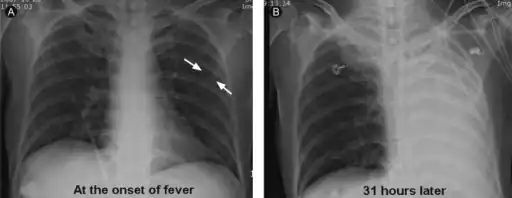

Atelectasis.

It is a common misconception and pure speculation that atelectasis causes fever. A study of 100 post-op patients followed with serial chest X-rays and temperature measurements showed that the incidence of fever decreased as the incidence of atelectasis increased.[4] A recent review article summarizing the available published evidence on the association between atelectasis and post-op fever concluded that there is no clinical evidence supporting this speculation.[5]